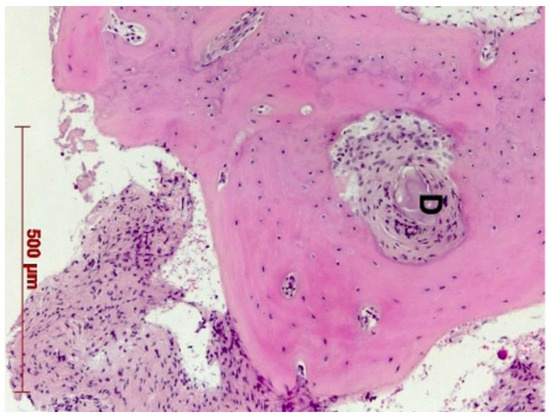

3.1. Bone Quality